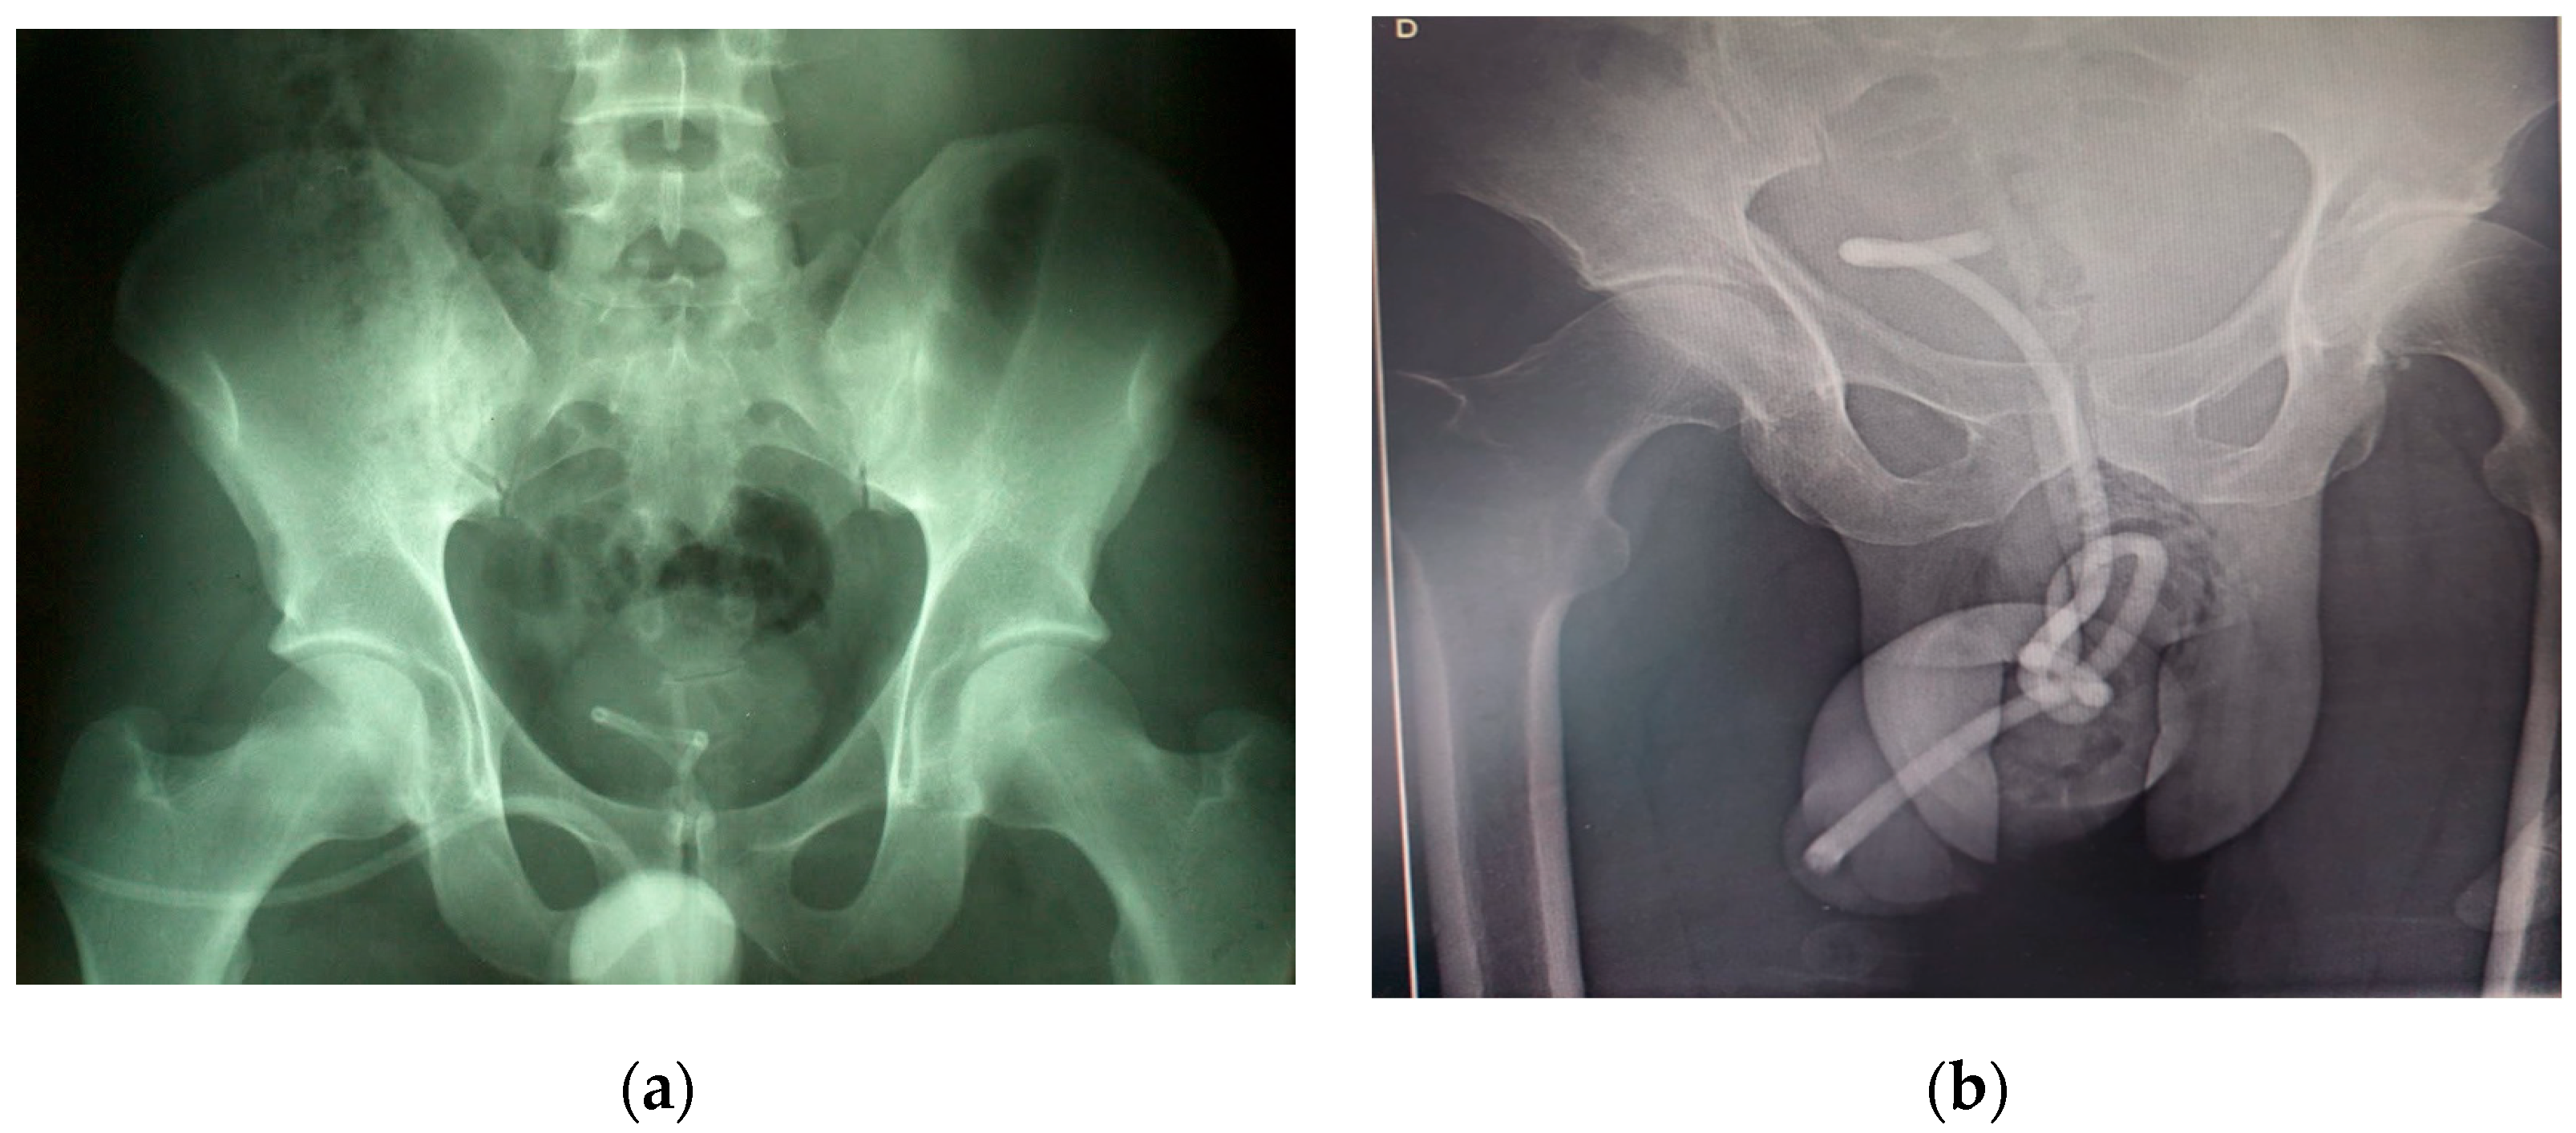

| Case 1 | 19 | male | Electric wire | urethra/ bladder | urethral pain, hematuria, urgency | self-catheterization | KUB X-ray |

| Case 2 | 53 | male | Electric wire | urethra/ bladder | urethral pain, hematuria, urgency, urinary retention | sexual arousal | KUB X-ray |

| Case 1 | Yes | Endoscopic | Bipolar endoscopic (urethra) and laparoscopic (suprapubic) Approach | 40 min | epidural | Yes, Amoxicillin |

| Case 2 | Yes | Open | Cystotomy | 45 | epidural | Yes, Ceftazidime |